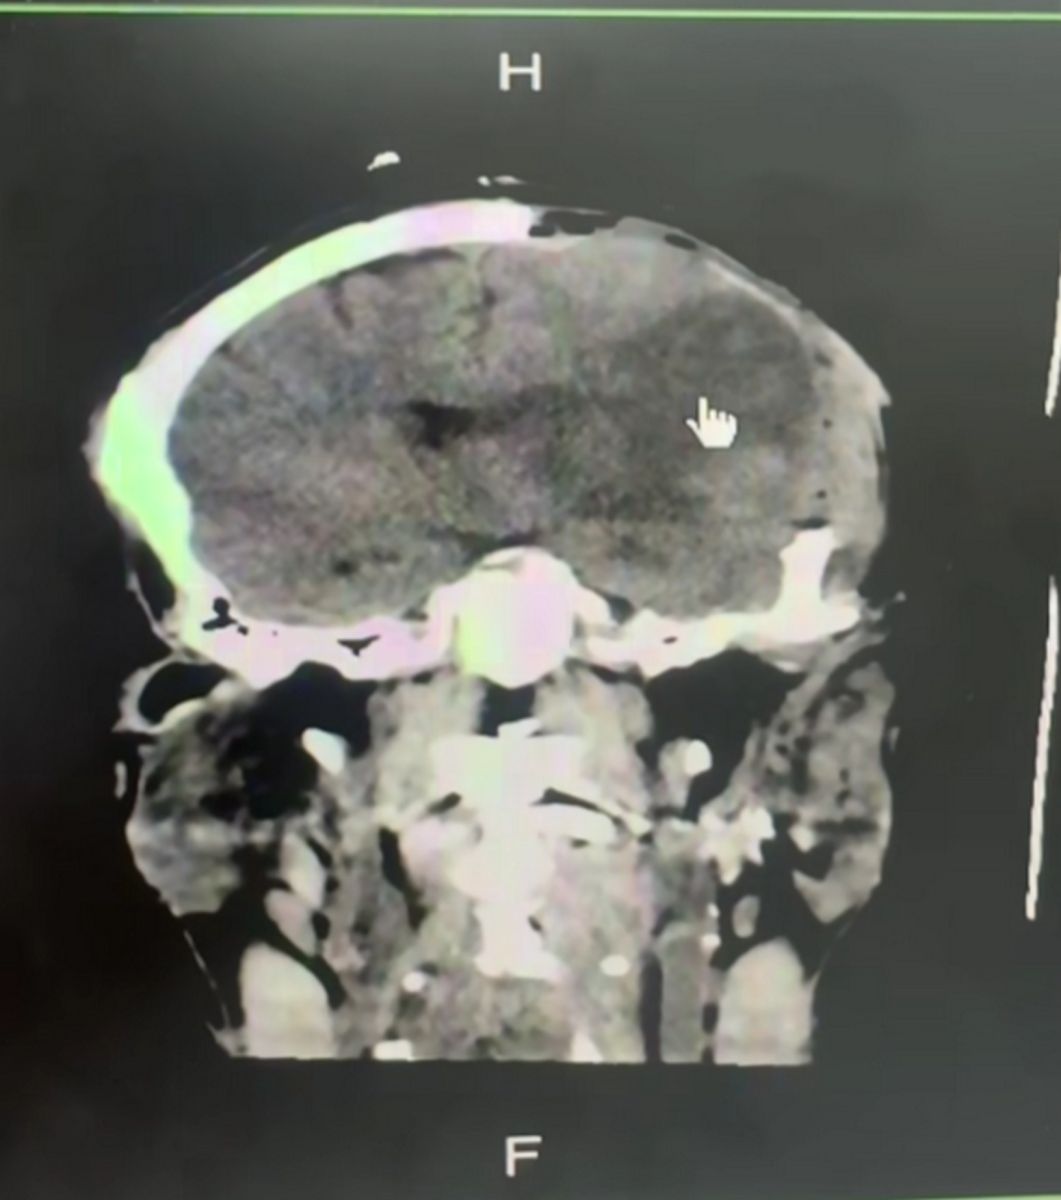

ผลซีทีสแกนพบสมองตายบางส่วน เส้นเลือดที่ไปเลี้ยงสมองจะมีอยู่ 4 เส้น หน้าขวา หน้าซ้าย ที่หายไป หลังขวา หลังซ้าย แต่คนไข้รายนี้ เหลือ 3 เส้น กรณีนี้เกิดจากเส้นเลือดที่คอปริแตกเซาะแล้วลิ่มเลือดไปอุดตันเส้นเลือดของตัวเอง และเเกิดขึ้นในเวลากลางคืนเกิน 8 ชั่วโมง จนสมองตายเป็นสีดำ เลยเวลาที่จะทำอะไรได้นอกจากการขยายกะโหลกเพื่อเพิ่มโอกาสรอด เปิดกะโหลกไว้เพื่อลดแรงดันในสมอง

จึงทำให้เคสนี้มีสมองตายในข้างซ้าย ซึ่งอุทาหรณ์จากเคสนี้ การนวดการคลึงคอแรงๆ จะทำให้เส้นเลือดเราปริแตกแล้วก็ตัน เรียกว่า อาเทอรีดีสเซสชัน